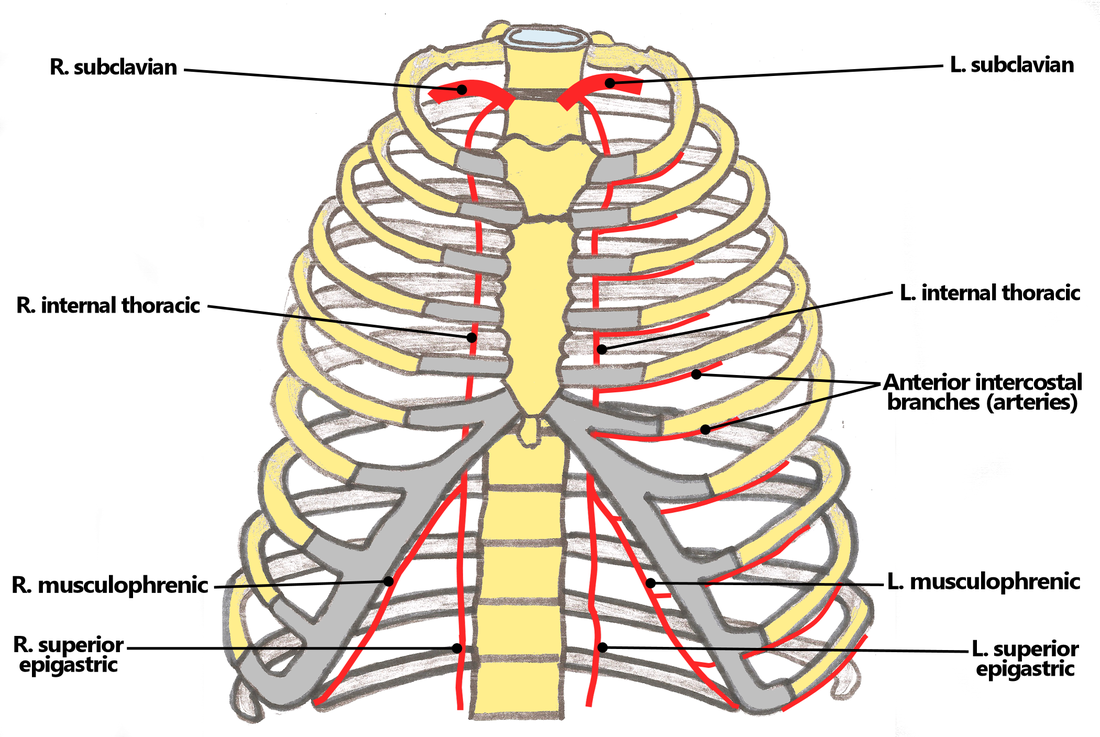

- Blood supply to the rib cage originates from what 2 places?

- what 2 arteries supply the intercostal spaces of the rib cage

- what branch off of the subclavian artery goes down specifically to the diaphragm?

aorta and subclavian artery

Anterior and posterior intercostal arteries

notice how branches from the aorta go around and supply the rib cage

the internal thoracic artery

look at picture

study picture

Identify/describe the intercostal artery pathway?

- Intercostal arteries/veins run in the ___________ aspect of

the intercostal space?

- They are ________ to the “superior rib” of the intercostal space?

- Collateral branches of intercostal arteries/veins run in the _________ aspect of the intercostal space

superior aspect

inferior

inferior

Anterior intercostal arteries:

- These arteries branch from where?

- then this originates from where?

internal thoracic artery

- Internal thoracic artery originates from subclavian artery

the internal thoracic artery comes from the ____________ vein and then runs behind the anterior ________?

subclavian vein

anterior sternum

notice the internal thoracic artery coming down right near the sternum

The Anterior intercostal arteries supply which intercostal spaces?

- The lower intercostal spaces supplied by what?

1-9

posterior intercostal arteries

notice how the intercostal arteries run superior and inferior in the intercostal spaces

look at all the arteries and their relationship

look at picture

what artery may be used as a bypass graft?

the left internal thoracic artery